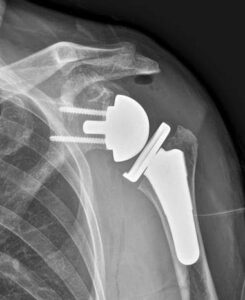

Visitations at different centres helps in exchange of ideas, learning and discussing new Techniques. Three day visitation to different centres in Seoul, S Korea for Shoulder Replacement was a wonderful way to interact with leading shoulder surgeons of South Korea and understanding their perspective regarding management of Shoulder Problems.